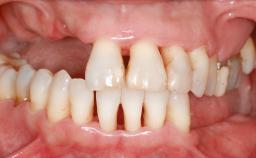

Ridge Preservation and Implant Placement for a Fixed Dental Prosthesis After a Car Accident

It is well known to clinicians that any removal of teeth will, over time, cause the dimensions of the alveolar ridge to be reduced by resorption of the bundle bone and by changes related to external modeling. This development is particularly evident in the crestal region with its thin buccal bone that consists of bundle bone almost entirely. The facial bone will rapidly resorb as blood supply from the periodontal ligament gets disrupted (Araújo and Lindhe 2005). There is no reason why traumatic tooth loss should not have the same consequences. It takes more than achieving implant osseointegration for a treatment outcome to be considered successful. No deficiency of bone or soft tissue is acceptable when an ideal esthetic outcome is the goal. Several articles (Sanz and coworkers 2011; Vignoletti and coworkers 2011) have reported on techniques of improving the alveolar ridge for implant treatment, notably focusing on protecting tissues from resorption.

| Soft Tissue Anatomy | Intact | Defective | |

| Bone Volume | Horizontally and vertically sufficient | Horizontally deficient | Deficient vertically or deficient vertically AND horizontally |